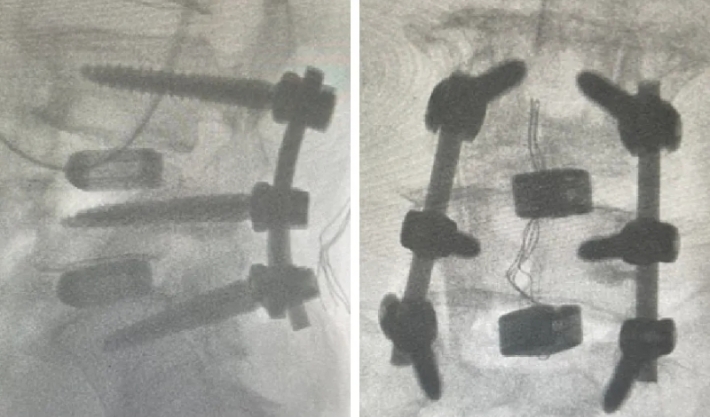

近日,新疆医科大学第六附属医院(新疆维吾尔自治区骨科医院)脊柱外三科在医疗技术上取得新的突破,成功为两位腰椎手术患者利用3D打印融合器实施了腰椎椎体间融合术,患者术后恢复良好。

随着人口老龄化趋势不断加剧,腰椎间盘突出症、腰椎管狭窄症、腰椎滑脱等已成为常见的退行性脊柱疾病之一,严重影响中老年人的生活质量和身心健康。腰椎椎体间融合术是解决退行性脊柱疾病的常用手术方式之一。然而,在老年人骨质疏松、骨含量低的情况下,容易发生植骨融合失败的后遗症。3D打印融合器能有效解决这一问题。这两例手术中所使用的融合器,是通过3D打印技术制造的一种新型的多孔钛合金椎间融合器,它的微观和宏观结构模仿了人体椎体的天然骨小梁,更加贴合人体结构。同时,进一步优化了材料表面,使其具有更好的生物相容性和成骨活性,能够帮助新生骨快速长入融合器,加速愈合。该融合器还很适合微创手术,不需要再植入自体骨或其他骨修复材料,不仅提高了治疗效果,还减少了患者的手术创伤。